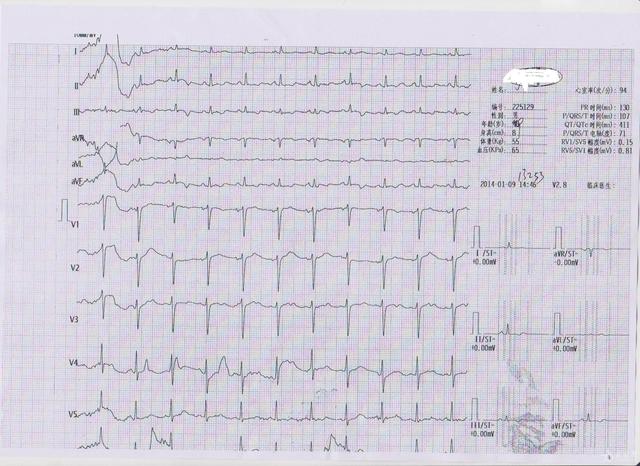

首先,人体的心脏24小时在不间断的跳动,在每个心动周期中,心脏的起搏点、心房、心室相继发生兴奋,伴随着生物电的不断变化。通过心电描记器可以从体表引出多种形式的电位变化的图形,这个图形就是心电图。所以心电图反应的是即刻的心律失常、心率、心肌缺血等情况,特别是对即刻的心律失常诊断意义最大(比如心电图抓住早搏、阵发房颤、室上速等)。

大多数情况下心电图的结果仅是参考意义。比如心律失常方面,即刻的正常心电图可能抓不住没发作的早搏、阵发房颤、室上速等,但不代表就没有这些心律失常。再如心肌缺血方面,一个冠心病的患者,在心绞痛不发作时,心电图可以完全正常,不能因为心电图正常就排除冠心病。所以临床上常用心电图结合动态心电图的检查方法,可以更好的明确诊断。

当然,有器质性心脏病的患者,心电图常更多的表现出异常,如冠心病患者多出现动态ST-T改变、异常Q波、左束支传导阻滞等;心脏扩大的患者多出现异常P波、左心室或右心室肥大的心电图表现等。作为常规筛查手段,心电图还是具有较好的参考价值。